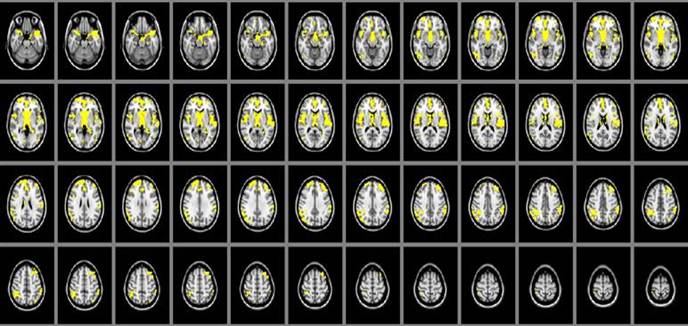

The cerebral gray matter density in SIVD patients were found significant decreasing than that of the normal controls in brain regions of thalamus, parietal lobe, frontal lobe and temporal lobe (P<0.05). (Table 2, Figure 1)

Figure 1

Area of cerebral gray matter density alteration in SIVD patients detected by MRI is shown in yellow color, including thalamus, parietal lobe, frontal lobe and temporal lobe, compared with control group.